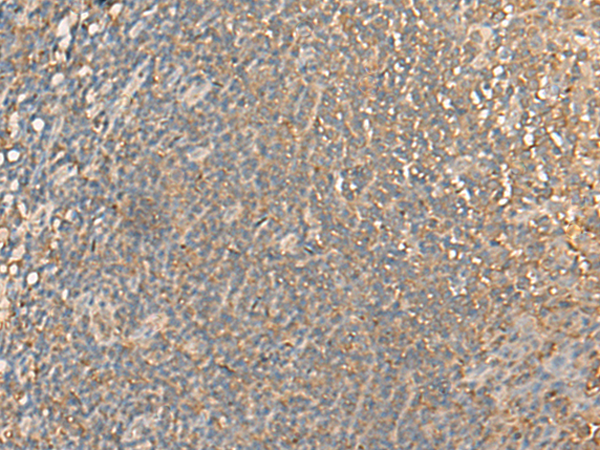

ELISA, WB, IHC |

IHC positive control: |

Human tonsil |

IHC Recommend dilution: |

25-100 |